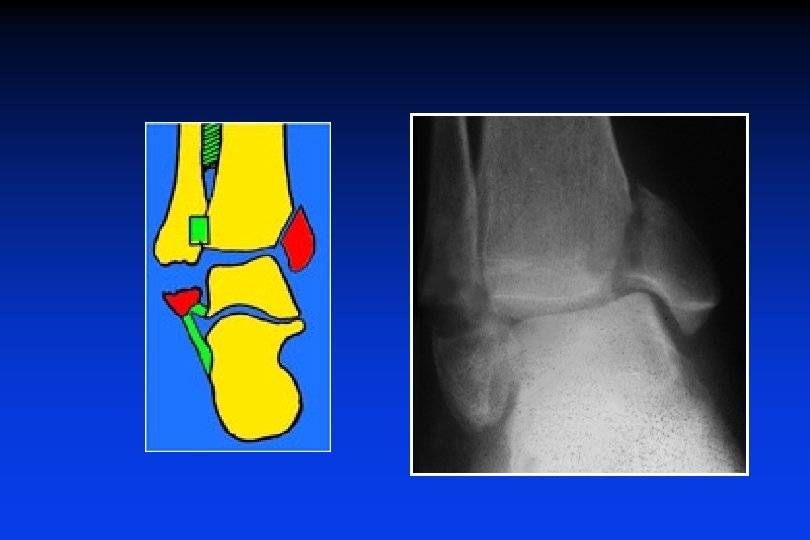

3/ FRATTURE IN ROTAZIONE ESTERNA sopra-legamentose (in abduzione) Stadio 1 : Fratture del malleolo interno (o LLI) Stadio 2 : Rottua del legamento peroneo-tibiale ant. , diastasi + Stadio 3 : Frattura del perone, obliqua in basso e indietro (alte o basse) Stadio 4 : Rottura del leg. peroneo-tibiale post, membrana interossea, diastasi +++ Fratt. di DUPUYTREN

3/ FRATTURE IN ROTAZIONE ESTERNA sopra-legamentose (in abduzione)

• Il perone si può rompere molto in alto (frattua di MAISONNEUVE)

Nome della lesione ? Commentare questo disegno: Meccanismo ? Elementi rotti?